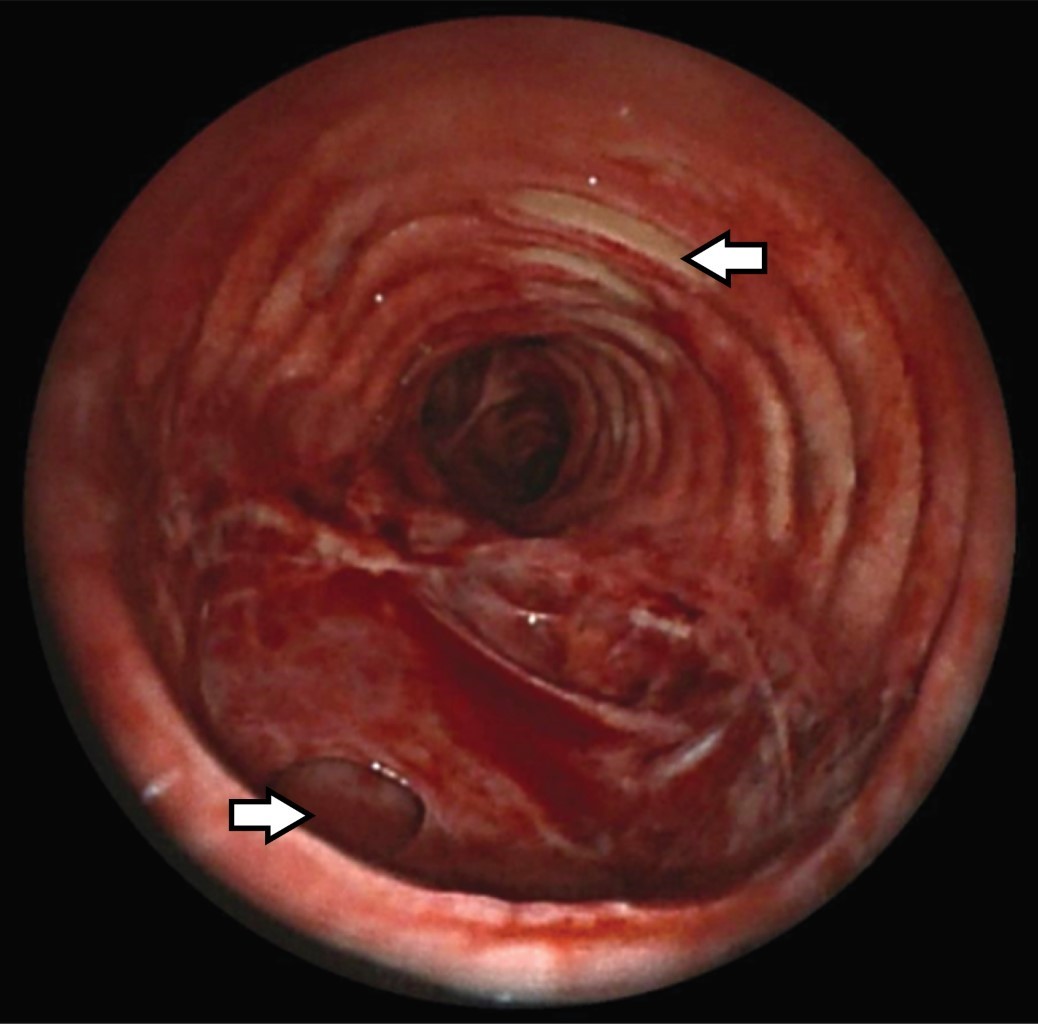

Femenino de 69 años. Ingresa a la Unidad de Terapia Intensiva (UTI) con diagnóstico de neumonía COVID-19, SDRA severo por Berlín con PaO2/FiO2 80 mmHg, pulsioximetría 92%, en ventilación mecánica invasiva (VMI) presión control 17 cmH2O, FiO2 60%, PEEP 12 cmH2O y frecuencia respiratoria 21/minuto. Al día 12 de VMI se realiza TP en la UTI con técnica de Ciaglia Blue Rhino.1 Se realiza incisión transversal de 2 cm a nivel del segundo anillo traqueal y punción entre el segundo y tercer anillo traqueal. A la aspiración se obtiene líquido citrino, por lo que se retira aguja y en una segunda punción se logra acceso efectivo. Se introduce cánula de traqueostomía de 8.5 mm y es conectada a la VMI; al momento presenta broncoespasmo tratado con broncodilatador y se realiza cambio de dispositivo a bolsa válvula mascarilla con reservorio; presenta resistencia a la ventilación con evidencia de enfisema subcutáneo masivo en tórax e hipoxemia por neumotórax a tensión bilateral; evoluciona a bradicardia y finalmente asistolia, se inician maniobras de reanimación, se realiza descompresión bilateral con aguja Punzocat no. 14, se asegura vía aérea con cánula orotraqueal de 8.5 mm al primer intento. Se logra retorno a la circulación espontánea con taquicardia sinusal e hipotensión, se colocan sondas endopleurales bilaterales y se procede a realizar fasciotomías pectorales para drenaje de enfisema subcutáneo; se observa en cámara de succión de Pleur-Evac® fuga aérea bilateral. Se recupera estabilidad hemodinámica a las 4 horas del evento y se realiza tomografía de tórax (Figura 1). La broncoscopia muestra laceración posterior de la tráquea (Figura 2). Por endoscopia se descarta lesión esofágica. El tratamiento inicial es conservador mediante ferulización traqueal durante 15 días. La broncoscopia de control muestra limitación de la perforación y tejido epitelizado; se decide cierre de lesión traqueal con parche de músculo esternohioideo izquierdo, se verifica aerostasia sin observar fuga (Figura 3). Se realiza traqueostomía a nivel de segundo y tercer anillo traqueal, y se coloca cánula de 7 mm Bivona® (Smiths Medical, Minnesota, EEUU), la rama distal queda pasando la perforación, se verifica aerostasia y hemostasia, se coloca drenaje Jackson Pratt® 10 mm (Bard, Covington GA USA) a lecho quirúrgico, con evolución radiográfica que demuestra expansión pulmonar, sin enfisema subcutáneo ni neumomediastino (Figura 4). Al quinto día del procedimiento quirúrgico cursó con broncoespasmo severo y obstrucción traqueal, presenta parada cardiaca sin lograr retorno espontáneo de la circulación.

Figura 2